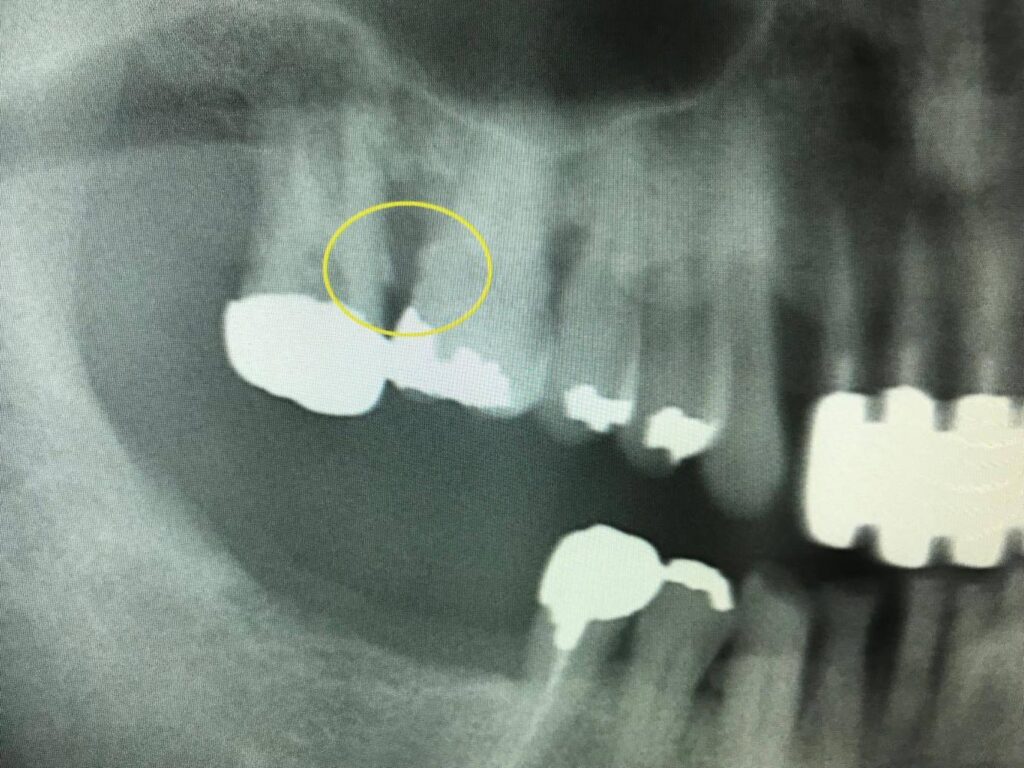

写真の黄色の円で囲まれている部分は歯石が付着し歯周病が進行している状態を示しています。

口臭・歯のぐらつき・咬合痛などの自覚症状を感じる時は重篤なことが多いので定期的な検診やレントゲン撮影を薦めています。